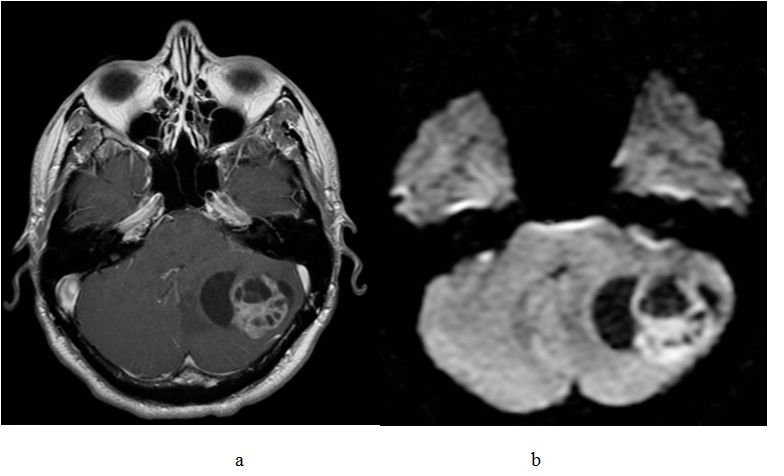

髓母细胞瘤的诊断主要依靠临床表现(颅高压症状、小脑症状、颅神经症状)和辅助检查。头颅MRI是诊断髓母细胞瘤重要的辅助检查方法。儿童的髓母细胞瘤大多起源于髓帆生殖中心的胚胎残余细胞,因此肿瘤常位于小脑蚓部,多为圆形实质性肿块,边界清,可见偏心性多发性囊变或坏死。而成人髓母细胞瘤被认为起源于一侧小脑半球的外颗粒层,因此常可发生于小脑半球,肿瘤多靠近小脑表面,内侧可见多发性小囊变、坏死和瘤旁水肿。大多数髓母细胞瘤在T1加权像上呈等信号或低信号,T2加权像上为混杂信号[3]。钆对比增强后,90%病灶呈现不均匀强化,另可存在坏死、出血或囊性变区域[4](图8a)。

由于第四脑室水平发生梗阻,可能出现脑积水。当出现脑膜播散时,在脑室内、脑部表面或椎管内,MRI可观察到明显的结节样强化或线样强化。目前,还有更多的磁共振成像技术如弥散加权成像(DWI)和氢质子磁共振波谱成像(1H-MRS)来辅助髓母细胞瘤的诊断。髓母细胞组织学特征为由细胞核大、细胞质稀少、核质比高的小圆细胞构成,排列紧密,细胞外间隙的体积小,限制了组织内水分子的弥散,因此在DWI上表现为高信号[5](图8b)。

图8. a.髓母细胞瘤在增强像上呈现不均匀强化,b.髓母细胞瘤在DWI上表现为肿瘤本身弥散受限,囊腔不受限。[7]